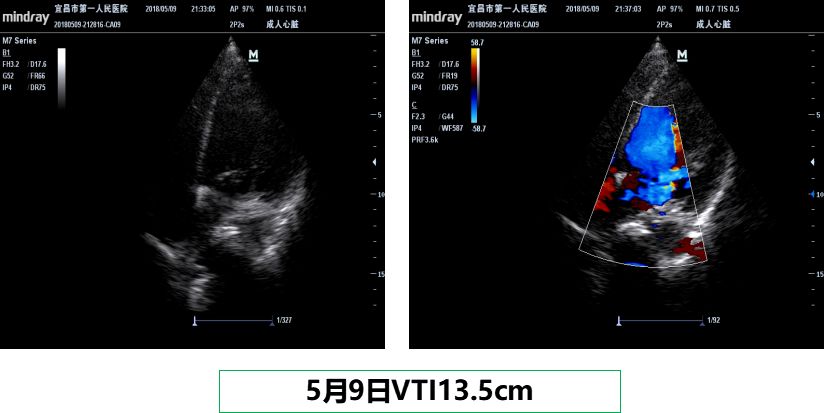

5月9日:ECMO第6天,一次性成功撤除ECMO